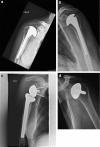

Figures